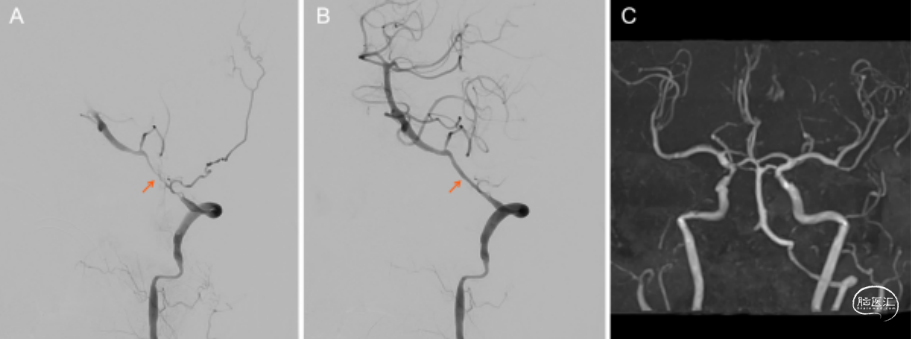

71岁男患,既往高血压、糖尿病、房颤、风湿病史,突发头晕和构音障碍来诊。查体:右侧眼睑下垂、共济失调。影像学检查见图1,给予阿司匹林+氯吡格雷双联抗血小板治疗,患者仍有症状进展,入院22天复查MRI及灌注见图1,入院第23天行椎动脉球囊扩张成形术(图2),手术顺利,术后患者症状改善。术后经颞动脉活检确诊巨细胞动脉炎(GCA),继续双抗+糖皮质激素治疗,症状改善。术后6个月随访良好(图2)。

图2. A:术前造影可见左侧椎动脉V3-V4重度狭窄,血流减慢;B:球囊扩张成形术后可见狭窄改善,血流恢复;C:术后6个月随访良好。